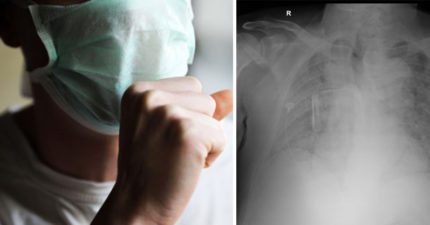

照X光白茫茫一片!醫搖頭:會越來越多 台男咳24小時身亡

May 25, 2021

台灣